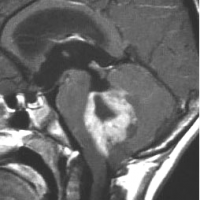

7歳児の小脳半球にある標準リスクの髄芽腫です。画像を一見すればこの髄芽腫は治るであろうと予測します。

手術で完全摘出し,退形成性髄芽腫の病理診断で,脳脊髄照射と局所照射54グレイ,シスプラチンベースの化学療法を6コース加えましたが,半年後に激しい播種再発を生じました。